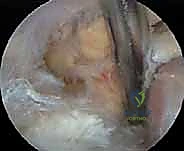

Diagnostic Arthroscopy and Intra Articular Pathology

The procedure commences with a standard posterior viewing portal. A thorough diagnostic arthroscopy of the glenohumeral joint is performed. If a paralabral ganglion cyst is the cause of spinoglenoid notch compression, the associated labral tear must be identified. An anterosuperior portal is established for instrumentation. The cyst is typically decompressed intra-articularly by excising the capsulolabral flap or probing the labral defect. Following complete evacuation of the mucinous cyst contents, the labrum is repaired using standard suture anchor techniques to prevent recurrence.

Spinoglenoid Notch Decompression

For isolated spinoglenoid notch entrapment (e.g., due to a hypertrophied spinoglenoid ligament or a cyst not amenable to intra-articular decompression), a posterior subacromial approach is utilized. The arthroscope is positioned in the subacromial space, viewing posteriorly. The interval between the posterior deltoid and the infraspinatus is developed.

The dissection follows the posterior aspect of the glenoid neck medially toward the base of the scapular spine. The spinoglenoid ligament is identified bridging the notch. Using arthroscopic scissors, the ligament is divided, taking care to avoid the suprascapular nerve and vessels that lie directly beneath it. Any residual extracapsular ganglion cyst is excised or marsupialized at this stage.

Clinical & Radiographic Imaging